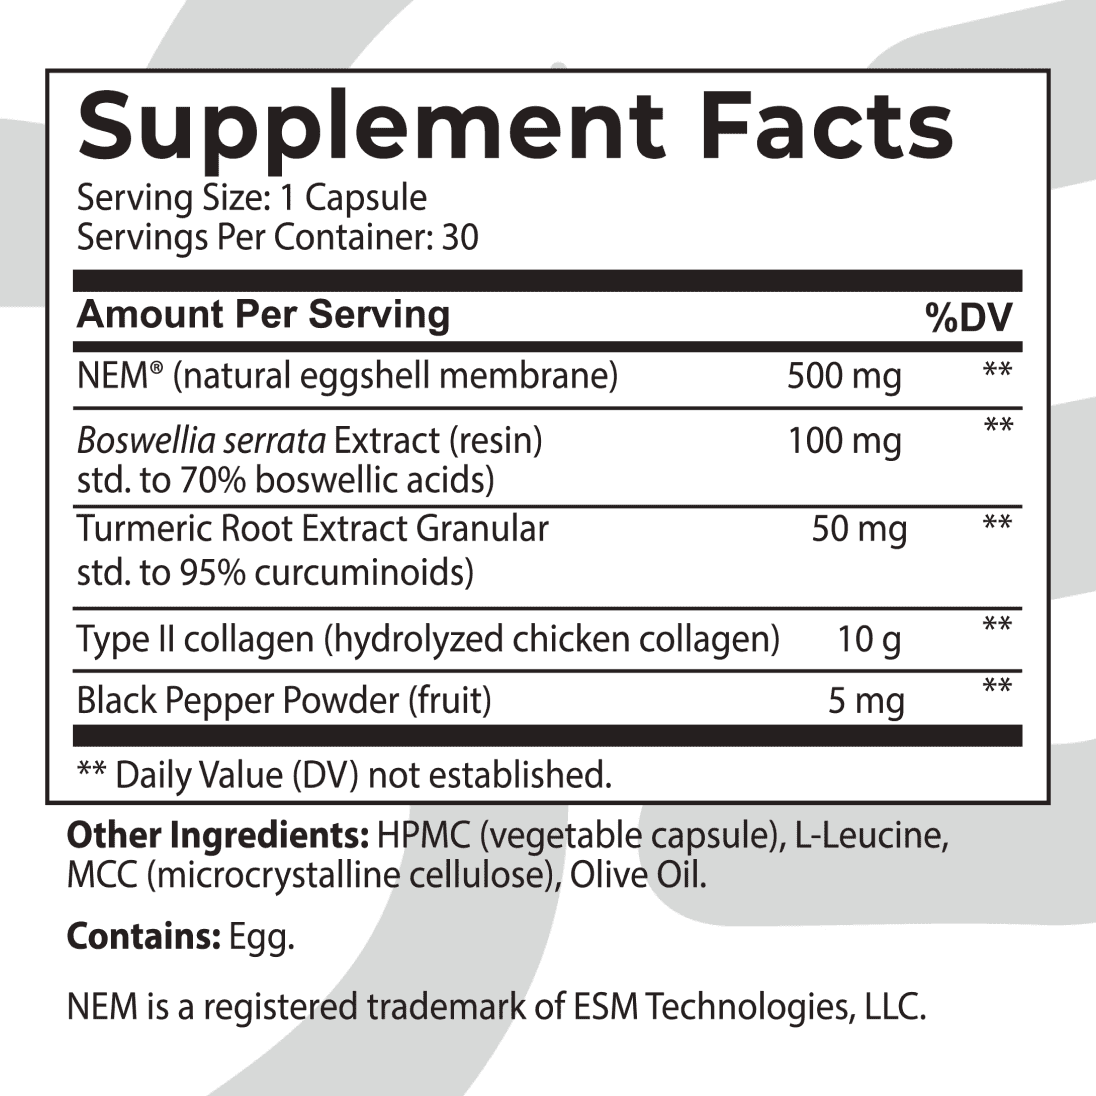

INGREDIENTS:

NEM® EGGSHELL MEMBRANE

NEM® is a clinically proven trademarked ingredient containing natural glycosaminoglycans and proteins critical for maintaining healthy joints. Recent studies show it significantly reduces inflammation, damage to cartilage and tissues, and bone decay and improves periosteal bone formation.* A Canadian clinical study showed statistically significant reductions in knee stiffness and soreness at 10, 30, and 60 days.* Researchers also observed rapid recovery from exercise-induced stiffness and discomfort with 500mg of NEM® daily.*

BOSWELLIA SERRATA

TURMERIC ROOT EXTRACT (95% CURCUMINOIDS)

Evidence shows the bioactive compound in Turmeric, curcumin, profoundly reduces joint discomfort, swelling, and stiffness. It helps block inflammatory molecules and enzymes from overactivity, alleviating the attack on your joints and giving your body a chance to rebuild and repair.*

COLLAGEN TYPE II (FROM CHICKEN STERNUM CARTILAGE)

Research shows type II collagen significantly improves joint discomfort, walking function, mobility, and quality of life.* Collagen diminishes immune T cells, which leads to swelling and stiffness.

BLACK PEPPER FRUIT

Piperine is a component of black pepper which has tremendous benefits in easing inflammation and joint discomfort. It also boosts Turmeric absorption, promoting maximum effectiveness.*

These powerful natural ingredients are clinically and scientifically proven to target specific joint functions and inflammation and improve functional joint health and overall well-being.

Check out our NEW Nation Health MD Joint Complex HERO’s ingredient lineup…

NEM® Eggshell Membrane: Researchers were thrilled with its results that they stated analysis demonstrated that NEM® supplementation could considerably help a significant number of patients. “NEM® has potential for a new natural therapeutic for joint and connective tissue disorders.”* Studies showed participants saw results in as little as 7-10 days and dramatic improvements with long-term use.

Boswellia, Turmeric, and Pepper: When combined, researchers found significant improvements in the ability to perform daily activities. They dramatically reduced stiffness and soreness by 37-39% and function scores by 30%. Boswellia considerably improves knee joint function by dramatically reducing immune markers, swelling, and discomfort, allowing better freedom of movement.***

Collagen Type II: A major cause of joint swelling, discomfort, and disease is from overactive immune markers called T cells that react with an antigen in your joint capsule. These T cells trigger immune cytokines that stimulate synovial fibroblasts (bone-producing cells) and chondrocytes (cartilage cells) to secrete enzymes. These enzymes degrade peptidoglycan and cartilage, which leads to bone destruction. Immune markers also stimulate bone breakdown, promoting nitric oxide synthase (iNOS), further tearing down bone.* Type II Collagen is an enemy of this process. Studies showed remission of disease in patients supplementing with Type II Collagen.*

EFFECTIVE INGREDIENTS: NEM® Eggshell Membrane, Boswellia serrata Resin Extract (70% boswellic acids), Turmeric Root Extract (95% curcuminoids), Collagen Type II (from chicken sternum cartilage), Black Pepper Fruit.

CONTAINS: Egg.

DIRECTIONS: As a dietary supplement, adults take one (1) capsule daily. For best results, take with 6-8 fl oz of water or as directed by a healthcare professional. Store in a cool, dry place.

SAFETY FACTS: Do not exceed recommended dose. Pregnant or nursing mothers, children under the age of 18, and individuals with a known medical condition should consult a physician before using this or any dietary supplement.

WHAT ARE THE EFFECTIVE INGREDIENTS IN NATION HEALTH MD JOINT COMPLEX?

WHAT ARE THE EXPECTED EFFECTS OF EACH INGREDIENT IN NATION HEALTH MD JOINT COMPLEX?

NEM® Eggshell Membrane – NEM® is a clinically proven trademarked ingredient containing natural glycosaminoglycans and proteins critical for maintaining healthy joints. Recent studies show it significantly reduces inflammation, damage to cartilage and tissues, and bone decay and improves periosteal bone formation. A Canadian clinical study showed statistically significant reductions in knee stiffness and soreness at 10, 30, and 60 days. Researchers also observed rapid recovery from exercise-induced stiffness and discomfort with 500mg of NEM® daily.

Boswellia serrata – Boswellia boasts several terpenoids with powerful anti-inflammatory properties that reduce joint swelling and discomfort. Studies show Boswellia considerably improves knee joint function and may start working in as little as 7 days.

Turmeric Root Extract (95% curcuminoids) – Evidence shows the bioactive compound in Turmeric, curcumin, profoundly reduces joint discomfort, swelling, and stiffness. It helps block inflammatory molecules and enzymes from overactivity, alleviating the attack on your joints and giving your body a chance to rebuild and repair.

Collagen Type II (from chicken sternum cartilage) – Research shows type II collagen significantly improves joint discomfort, walking function, mobility, and quality of life. Collagen diminishes immune T cells, which leads to swelling and stiffness.

Black Pepper Fruit – Piperine is a component of black pepper which has tremendous benefits in easing inflammation and joint discomfort. It also boosts Turmeric absorption, promoting maximum effectiveness.